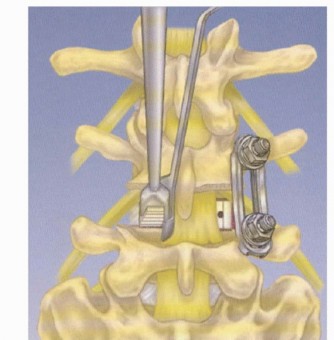

DEFINITION Minimally invasive transforaminal lumbar interbody fusion (MIS TLIF) is a modification of the Wilt…